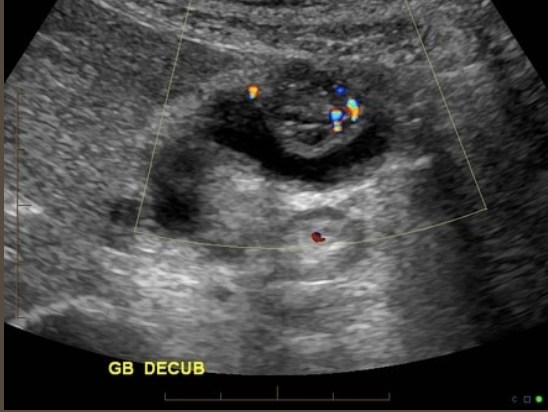

Adenomyomatosis → benign, common exaggeration of inner layer of GB wall (mucosal layer)

clinical hx: middle-aged female

s/sx: asymptomatic

2D US: non distended GB, mucosal layer thickening with cystic spaces, focal thickening at fundus more common, produces comet tail artifact, usually on anterior wall, can produce hourglass change of GB shape

color doppler: avascular, can have hypovascular pattern in hypoechoic lesion (adenomyoma)

DDX: emphysematous GB, porcelain GB